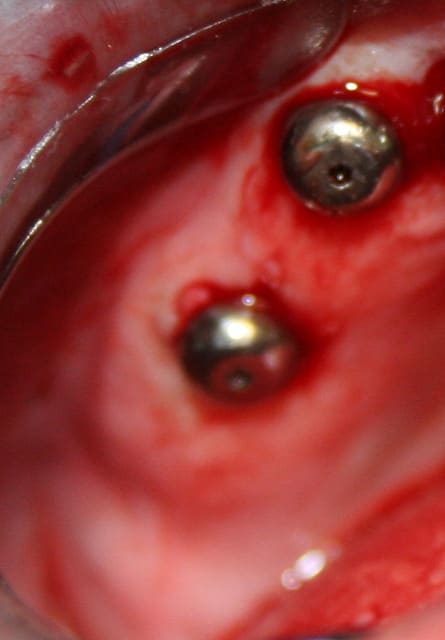

et pour le fun, ce que j'ai fait ce matin en 15min là aussi...

la patiente ne voulais pas faire de sinus lift car elle avait eu pas mal de pb de ce côté là...

donc, j'ai posé l'implant à raz le long du plancher sinusien

et bien, je souhaite bien du plaisir à qui doit poser un implant de la sorte à main levée en prenant à la fois en compte le sinus et l'émergence du col de l'implant pour ne pas avoir de pb pour faire la prothèse...

à part y aller millimètre par millimètre et prendre des radios à chaque fois....

P.S: j'ai quand même vérifié après l'insertion finale que je pouvais connecter un transfert...bilan, aucun problème!